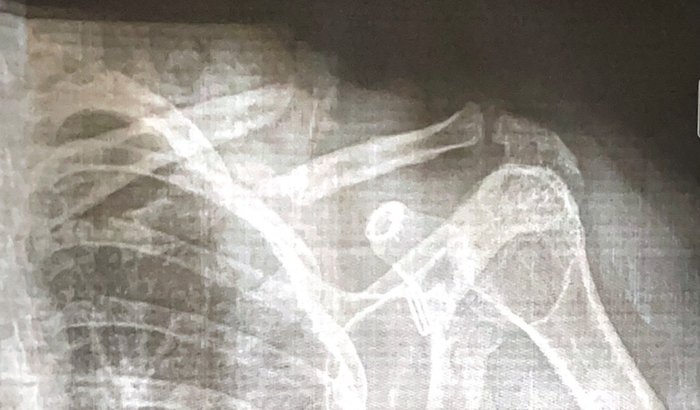

Criei essa Vakinha, pois preciso arrecada o valor de $10.000,00 pra uma cirurgia de clavícula, em 25 de outubro foi o acidente, como a espera pelo Sus é um tanto demorada devido a classificação da gravidade. Sou acadêmica de ciências ambientais, estou no último semestre do meu curso na universidade federal, estava preste a iniciar meu tcc quando tudo aconteceu, e hoje me vejo dependendo do estado e se não agir o mais rápido possível correndo o risco de perder minha tão sonhado conclusão. Desde já agradeço, e peço a Deus que abençoe cada um pela sua ajuda.